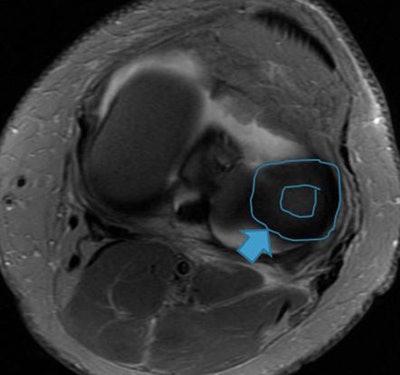

"Acute and often overlooked lateral patellar dislocation can be established with magnetic resonance imaging because of its characteristic pattern of injury. In particular, the integrity of the MPFL [medial patellofemoral ligament] should be assessed carefully. This ligament is the most important passive stabilizer of the patellofemoral joint. The MPFL should be assessed on transverse images," she noted.